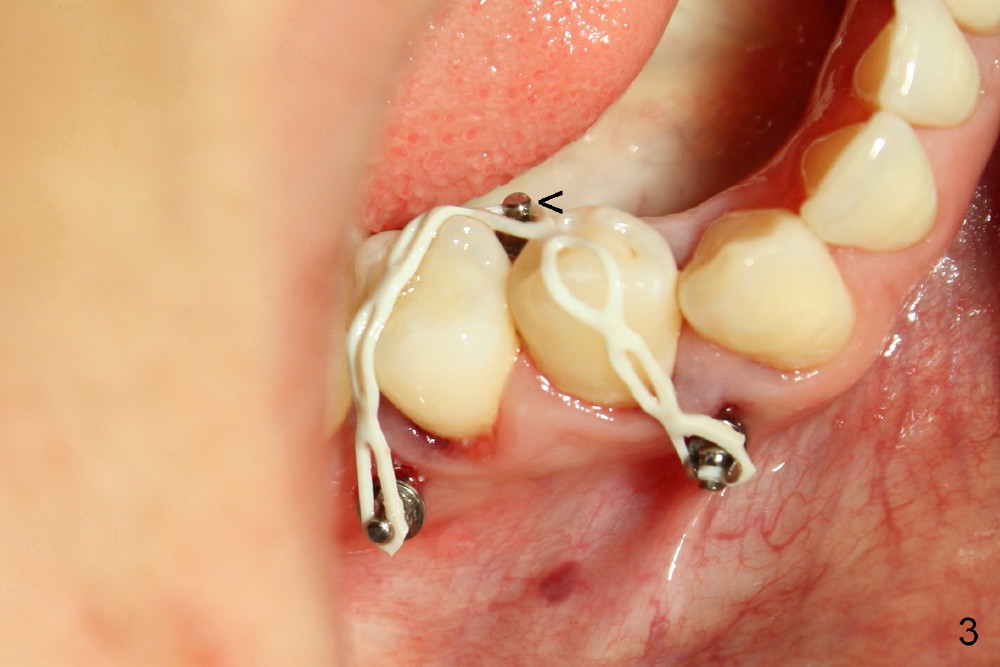

Twenty-seven-year-old Mickey has short clinical crowns in the maxilla (Fig.1). Two of the premolars (#4,5) have severe caries. When immediate implants were placed (Fig.2: I), there is no room to install abutments, probably due to the supraeruption of the opposing teeth (Fig.2 arrows). Three mini-implants (2 buccal (Fig.2), one lingual (Fig.3 <) were placed for intrusion.

But the lingual mini-implant fell out several times. What should we do?